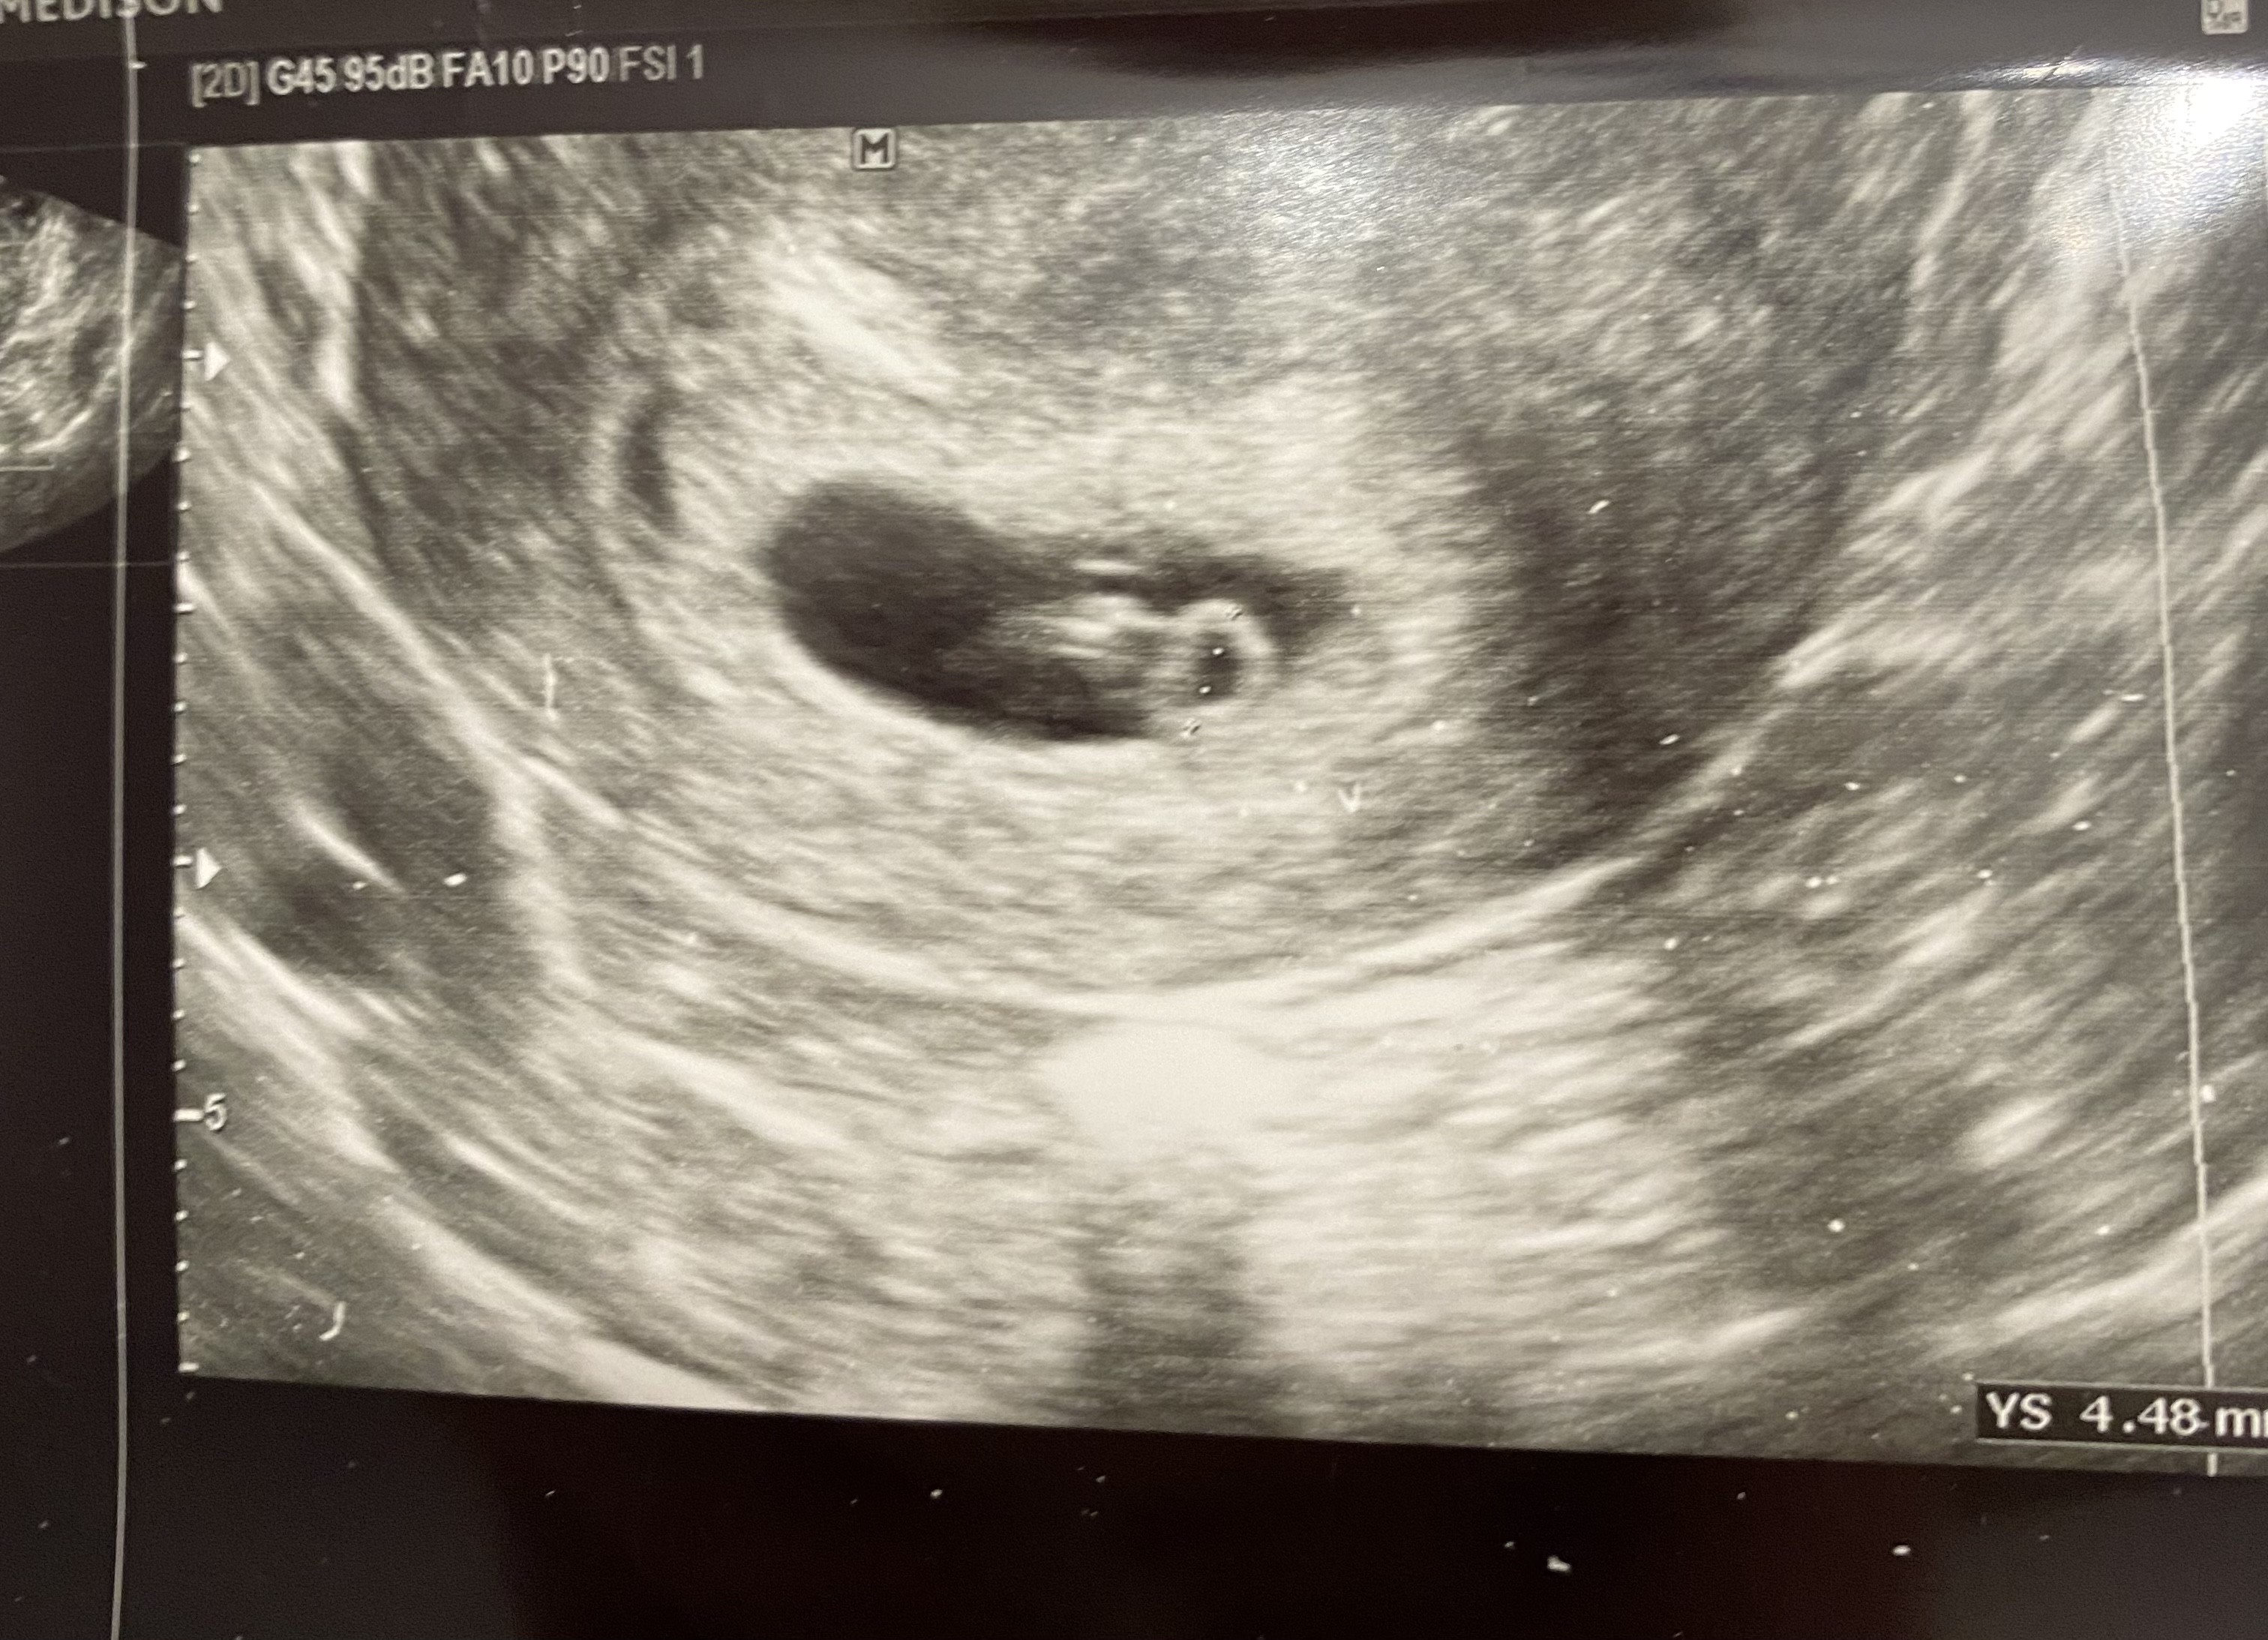

Hej dziewczyny, ja właśnie wróciłam z wizyty - ciąża młodsza o 3 dni, termin z OM na 18.11 , a z usg 21.11 ❤️

Nasz mały człowiek ma 1,1 cm i serduszko bije mu 159u/min 🥰 uroniłam łezkę jak usłyszałam jego bicie- niesamowite emocje!

• F27BADCB-F09D-403C-B8C3-D9D67CC876B7.jpeg

1,2 MB · Wyświetleń: 103